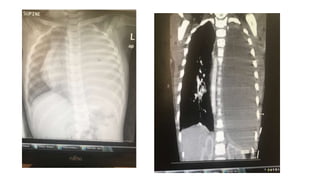

Chest US ,CT both suggest a pleural effusion (proteinacious) with

minimal septae

Chest US ,CTboth suggest a pleural effusion (proteinacious) with minimal septae